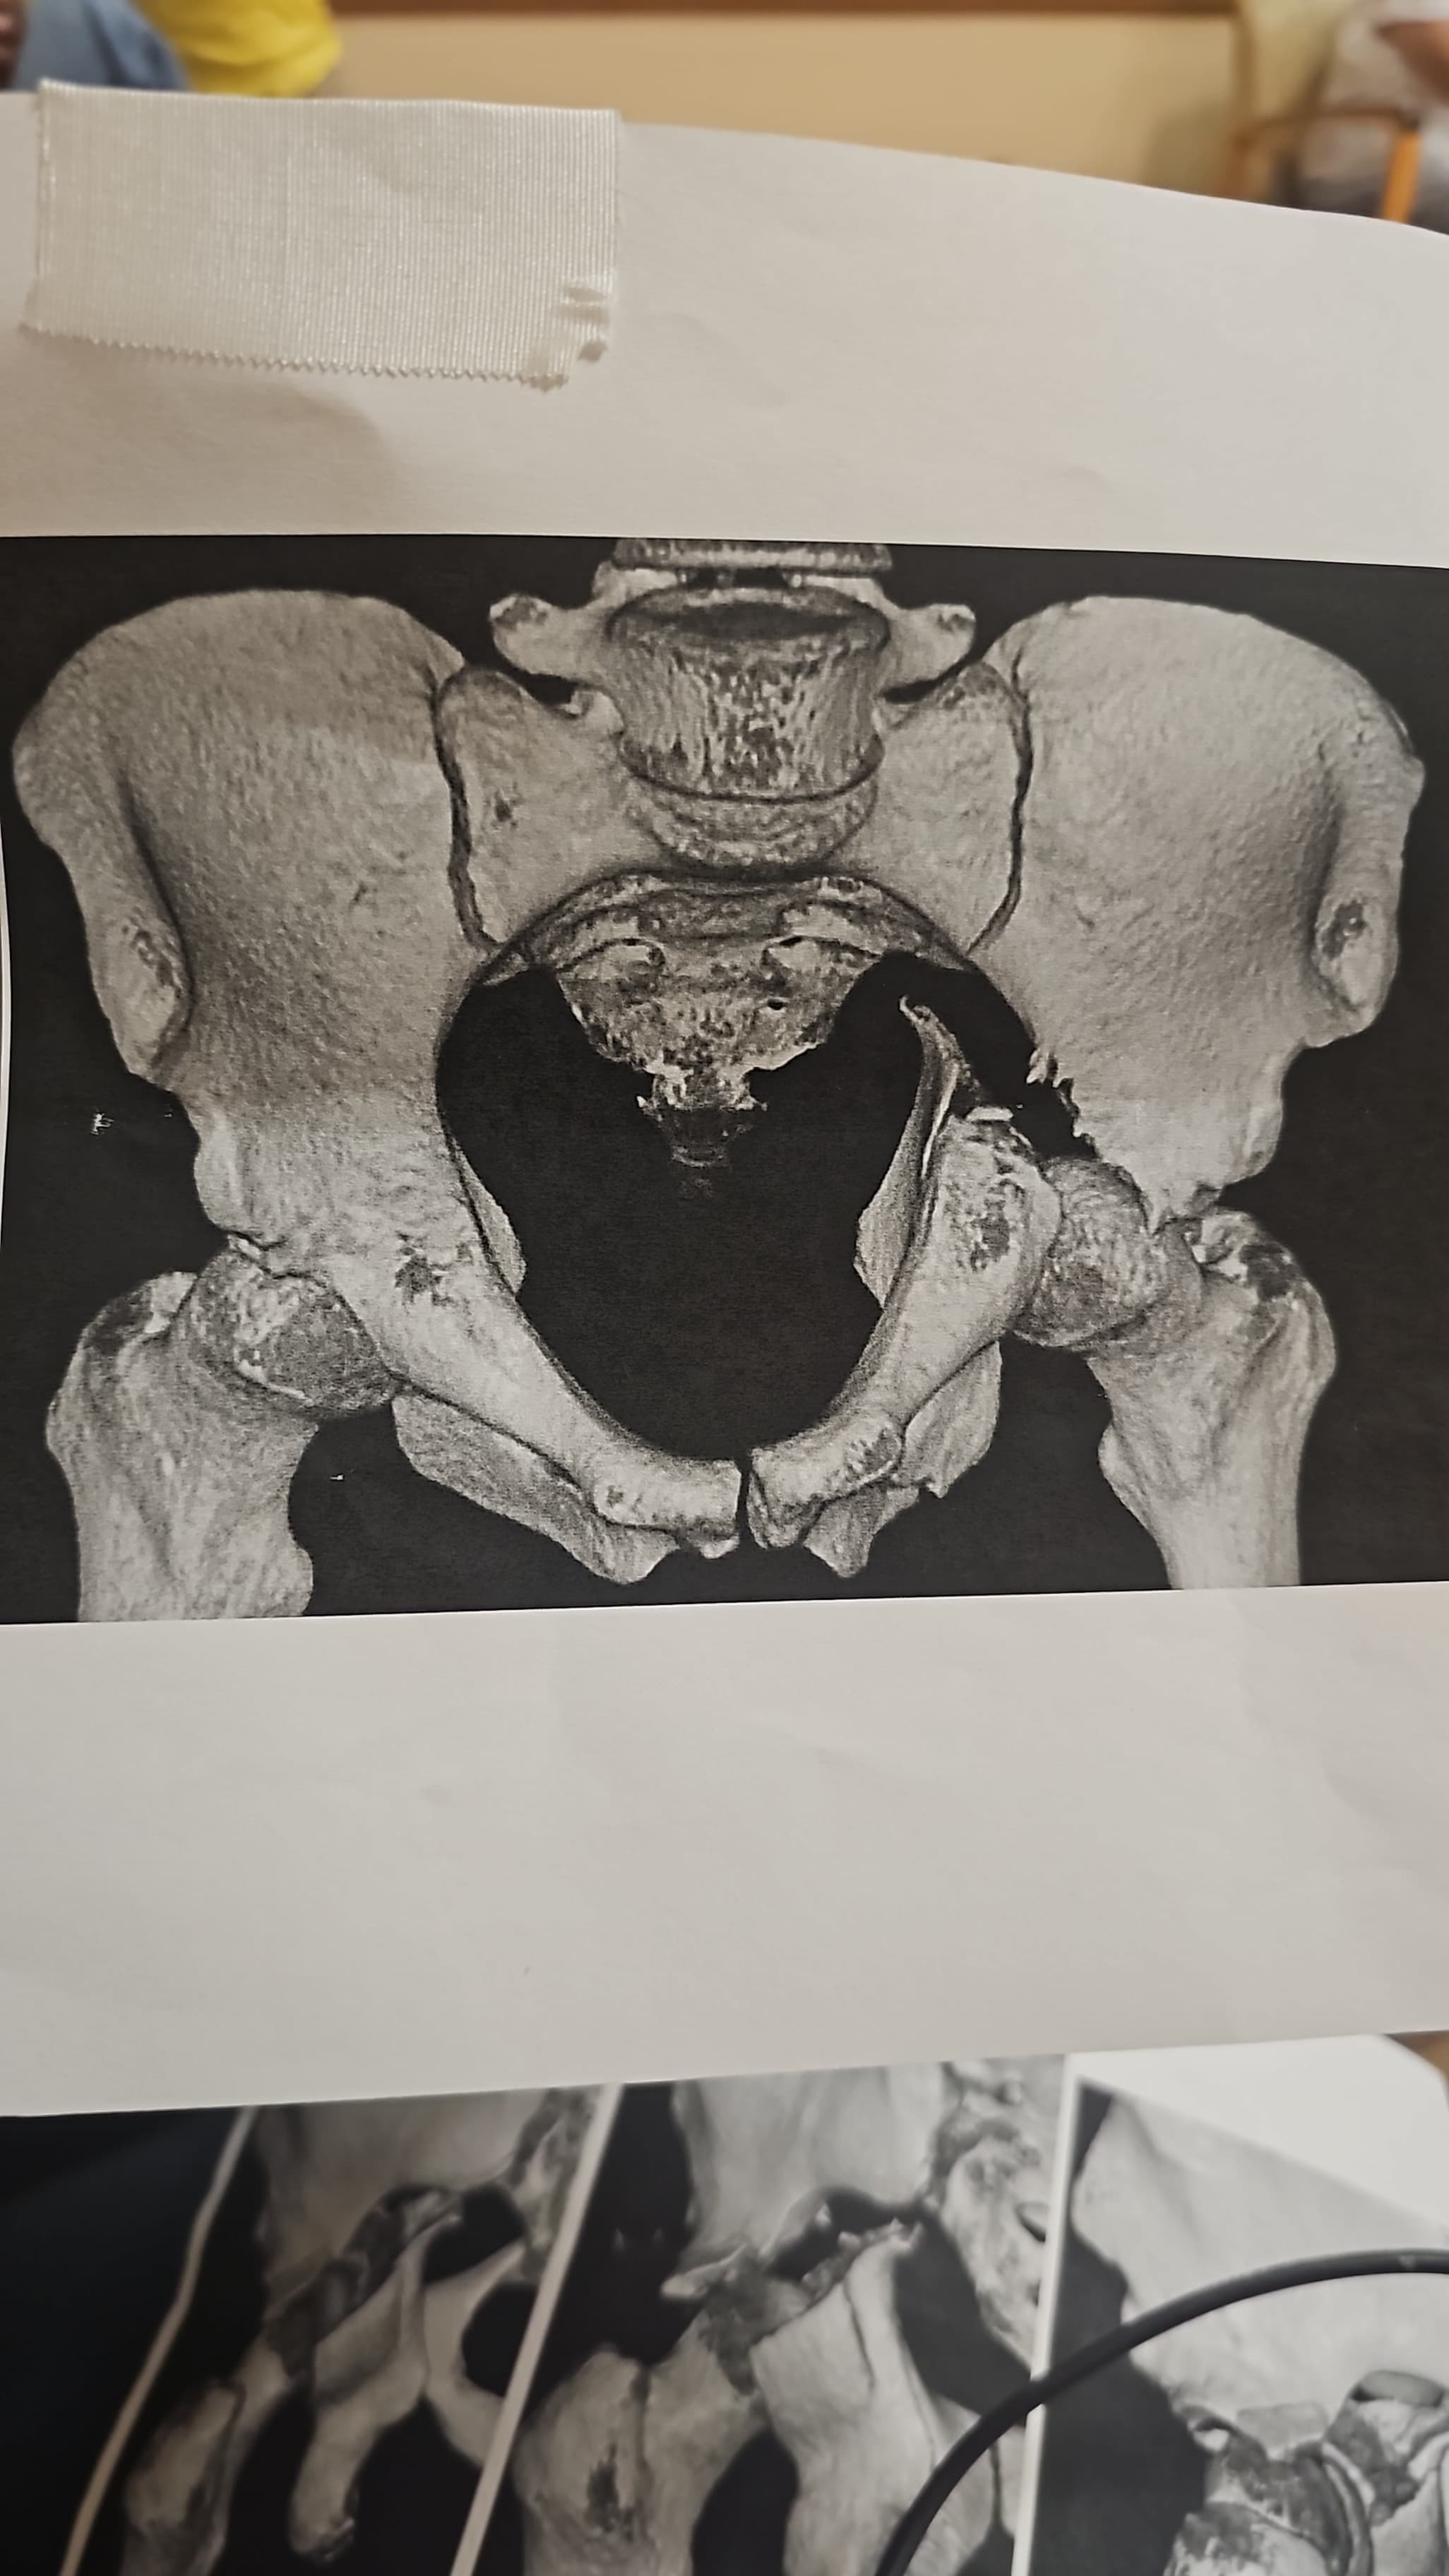

Alberto, my cousin and a beloved member of our family, was recently involved in a serious car accident caused by a drunk driver. The crash left him with a broken arm and a broken hip and severe damage nerve, and he has already undergone two surgeries. Right now, he is just beginning his long recovery journey is going to take him a while to walk and were gonna have to teach him how to walk all over again, and our family is doing everything we can to support him.